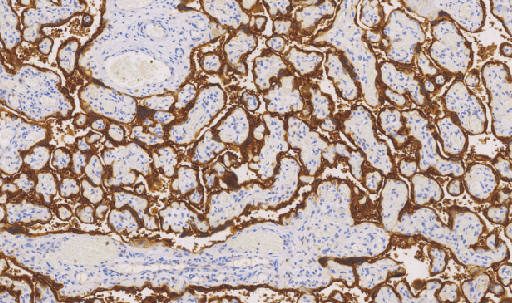

Human Chorionic Gonadotropin(HCG)鼠抗人绒毛膜促性腺激素单克隆抗体

HCG又叫绒毛膜促性腺激素。是胎盘滋养细胞分泌的一种糖蛋白,妊娠的绒毛滋养细胞表达较高。主要应用于绒毛膜上皮癌、葡萄胎 (恶性)的诊断。生殖细胞肿瘤的胚胎性癌、精原细胞瘤等有表达。在卵巢癌、乳腺癌、肺癌及恶性黑色素瘤中HCG也有表达

- 阳性部位:胞质

- 适用组织:石蜡组织

- 预处理:热修复